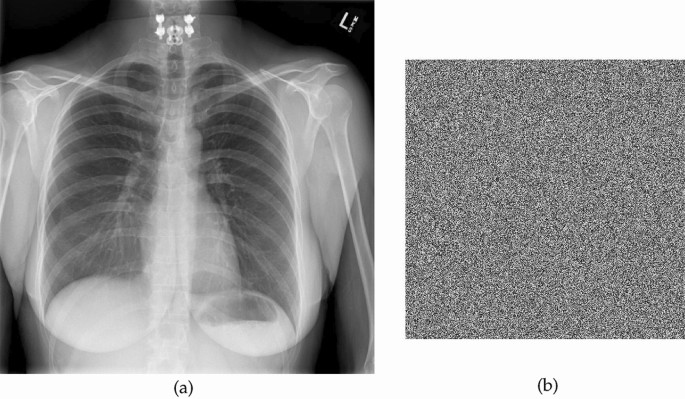

Image encryption

The utilization of the proposed S-box in the realm of encrypting medical images demonstrates a potential avenue for enhancing data security and privacy within healthcare systems. Strong protection against unauthorized access and online threats is required due to the delicate nature of medical images, which frequently contain sensitive patient information. When the innovative S-box is incorporated into encryption techniques, it offers a way to enhance the security of these priceless medical assets. The S-box enables the development of complicated encryption algorithms that thwart adversaries’ attempts to undermine the security of medical images by increasing the non-linearity and confusion aspects of encryption methods. In the constantly changing world of healthcare technology and information security, this novel technique has the potential to significantly protect patient privacy and guarantee the accuracy of medical data. We employed the CBC mode of AES to encrypt plain images with the proposed S-box. The corresponding images are displayed in Figs. 1, 2, 3, 4, 5, 6, 7 and 8. The Fig. 9 depicts the strength against salt and pepper noise with different intensity levels and Table 3 discusses the different tests for an image encryption.

Plain and cipher X-Ray image.

Histograms of plain and cipher X-Ray image.